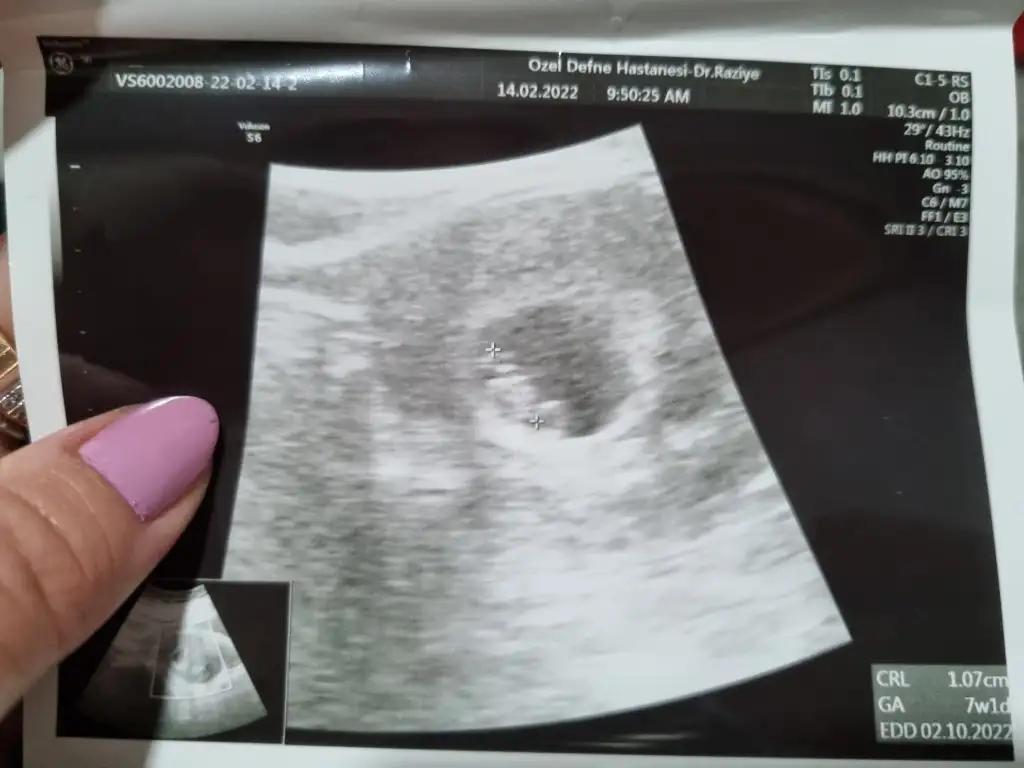

Hadi gözün aydinnn çok sevindim darısı bizim başımızaKızlar ben kalp atışını duydum bugün

Ayy ne güzel hayırlı olsunKızlar ben kalp atışını duydum bugün

Ayy maşallah maşallah Allah nazarlardan korusunİnşallah en kısa sürede sizde duyarsınız canım gerçekten çok güzel bir duygu

Duydum kızlar duydum şükürler olsun inşallah darısı bekleyenlerin başınaAman iyi iyi bende sürekli yatislardayim boşver